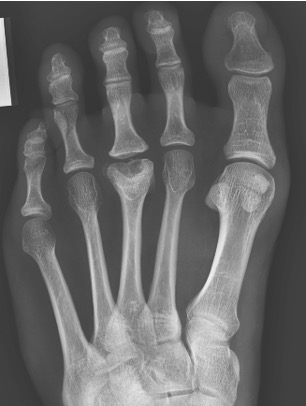

Plain standing radiographs offer a clear diagnosis in established cases (Figure 3).

Figure 3: established changes of Freiberg’s disease within the 3rd metatarsal head